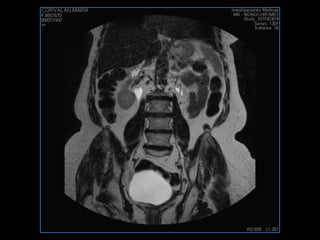

PROTOCOLO pelvis SAG T2, Y FAT SAT (FINOS) AXIAL T1  AX FAT SAT CON   GADOLINIO :  AX T1 Y COR T1 SAT: NO  FASE: RL THK: 3MM  COIL:  GAP: (FACTOR 1.4) 1MM FOV: 40 CM NEX:2 SINCRONIZACION RESPIRATORIA EN 3 O 4 CICLOS ALE